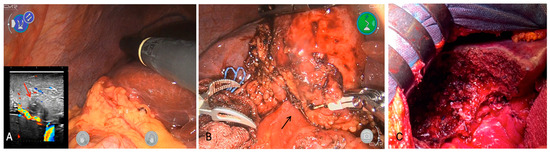

3.3. Treatment

3.3.1. Case 1

3.3.2. Case 2